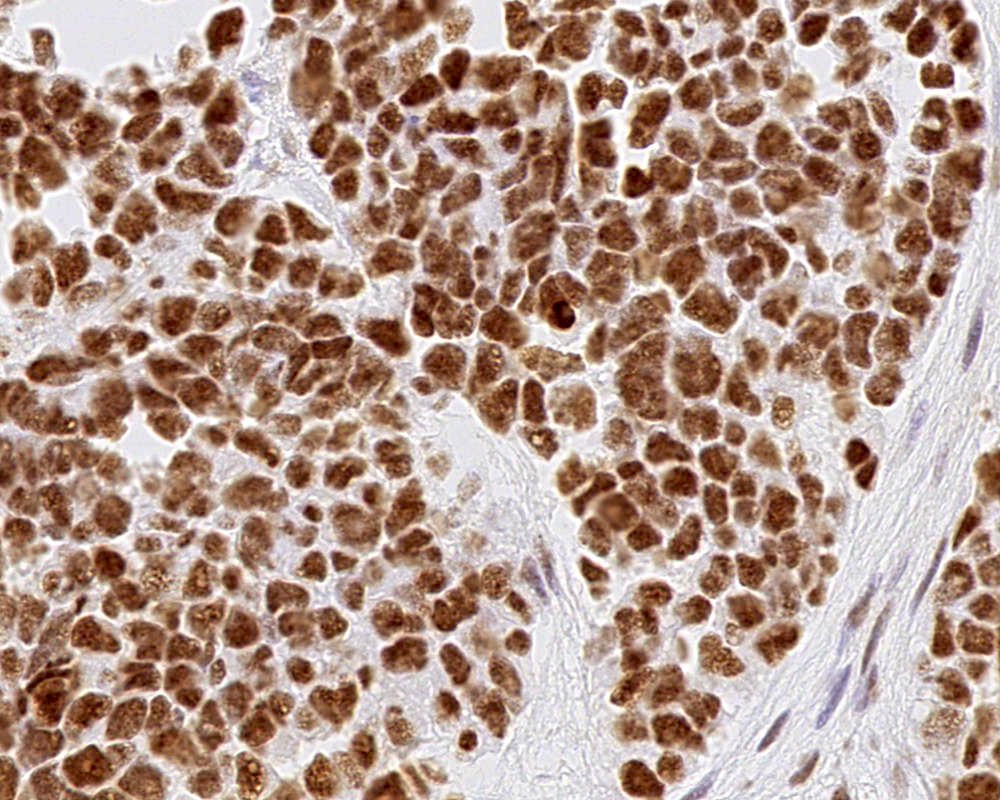

Microscopic (histologic) images

- Choroid plexus carcinoma (CPC, WHO grade 3):

- Frankly malignant

- High cellularity, hyperchromatic nuclei and nuclear pleomorphism

- Blurring of papillary pattern and solid arrangement

- Frequent mitoses (> 5/10 high power fields), necrosis, with or without brain invasion

- Choroid plexus carcinoma: p53 variable, SMARCB1 / INI1 and SMARCA4 retained nuclear expression